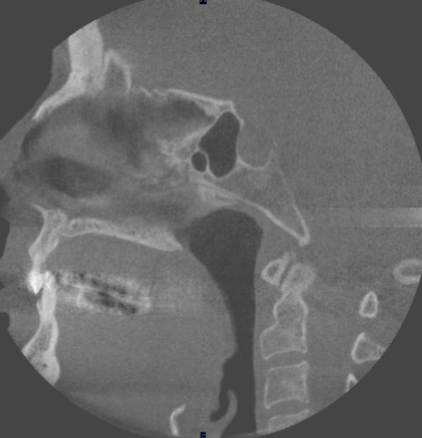

sagittal

what plane is this